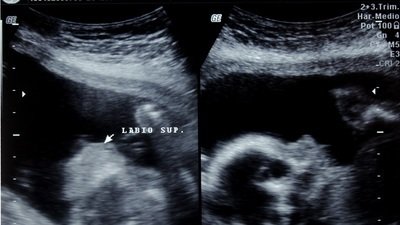

En el año 2008 acudí al Hospital General Regional 196 del Instituto Mexicano del Seguro Social para atenderme por un aborto involuntario consecuente a un embarazo anembrionico. Mientras estuve internada, tanto médicos como enfermeras me juzgaron pensando que yo había abortado por decisión propia, comenzaron a referirse a mi persona como " el aborto". Cuando leían mi expediente y pronunciaban las palabras "embarazo anembrionico" yo comenzaba a llorar, entonces cambiaban su actitud; me daban palmadas en el hombro y decían que "ya podría yo intentar nuevamente el siguiente año", que no llorara "porque asustaba a las otras pacientes."

En 2015, en la UMAE HGO 3 del CMN La Raza, también perteneciente al IMSS, perdí mi segundo embarazo debido a una colestasia intra hepática, hidropesía fetal, además de que presenté varios síntomas de Síndrome de Hellp, sin que este último se pudiera aseverar de manera definitiva.